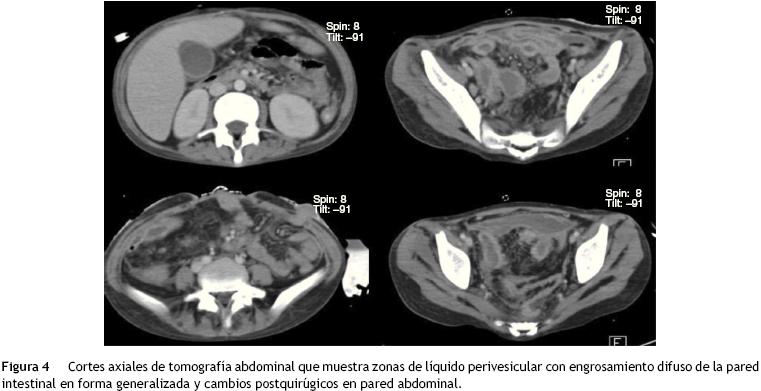

La tomografía de mediastino muestra disección por gas a través de las masas musculares, predominantemente en la región cervical, a nivel del tórax y de predominio axilar. En los segmentos inferiores se observa cómo el aire está prácticamente dibujando todo el trayecto de la aorta. Hay derrame pleural, predominantemente en el lado derecho, y el hígado se encuentra aumentado de tamaño (fig. 3). En la región media hay una diástasis de los rectos y cambios por la ileostomía realizada (fig. 4).